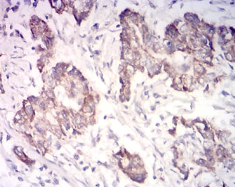

IHC    1/200 - 1/1000